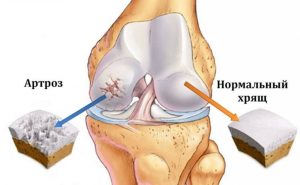

Коленный сустав образован бедренной и большеберцовой костями, покрытыми гиалиновым хрящом, а также менисками, связками и синовиальной оболочкой.

Хрящ выполняет роль амортизатора и обеспечивает плавное скольжение суставных поверхностей.

При гонартрозе:

• хрящ истончается и теряет эластичность

• ухудшается питание (трофика) тканей

• увеличивается трение между костями

• формируются костные разрастания (остеофиты)

• развивается воспаление (синовит)

В результате нарушается нормальная биомеханика сустава и появляется боль.